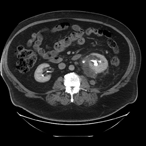

Massive retroperitoneal dedifferentiated liposarcoma in a young patient

Fernando X Moyon and others

Journal of Surgical Case Reports, Volume 2018, Issue 10, October 2018, rjy272, https://doi.org/10.1093/jscr/rjy272